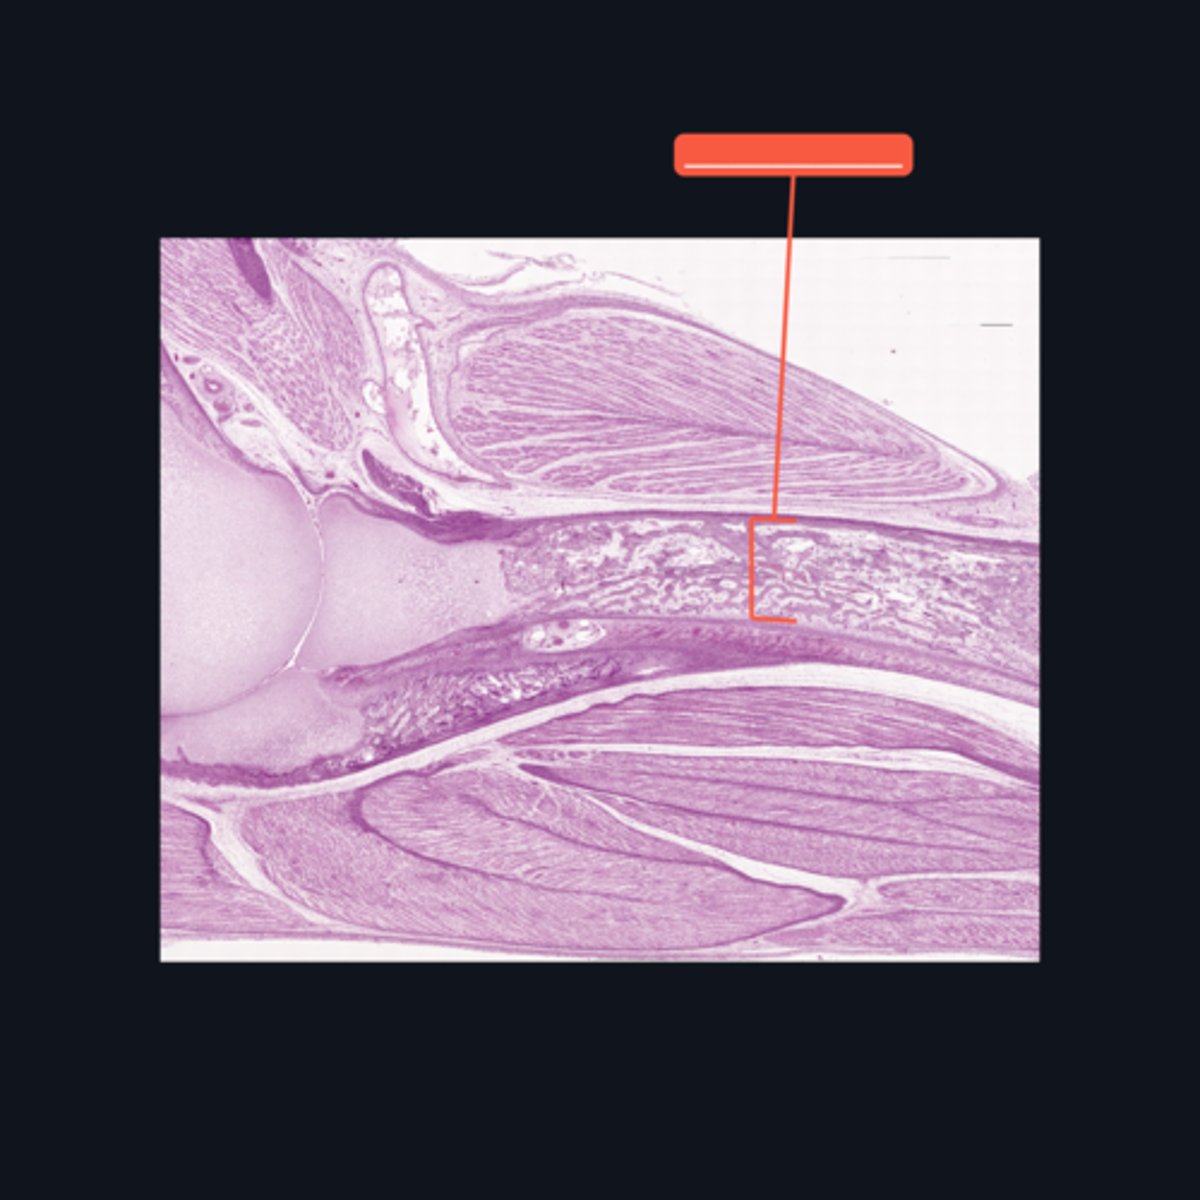

Medullary cavity

Identify the area encompassed by the bracket symbol, which is a hollow core that contains the developing blood cells and spongy bone spicules.